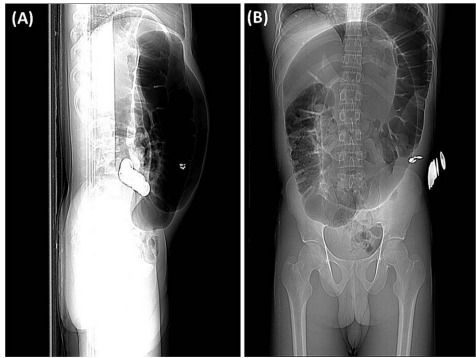

临床评估:通过腹部CT扫描确认"咖啡豆征"(coffee bean sign)和"肠系膜涡旋征"(mesenteric whirl sign)等典型影像学特征

CT扫描显示直径达10cm的扩张肠袢,伴有特征性黏膜皱襞消失。这些发现与急性闭袢性肠梗阻的典型表现相符,为紧急手术决策提供了依据。